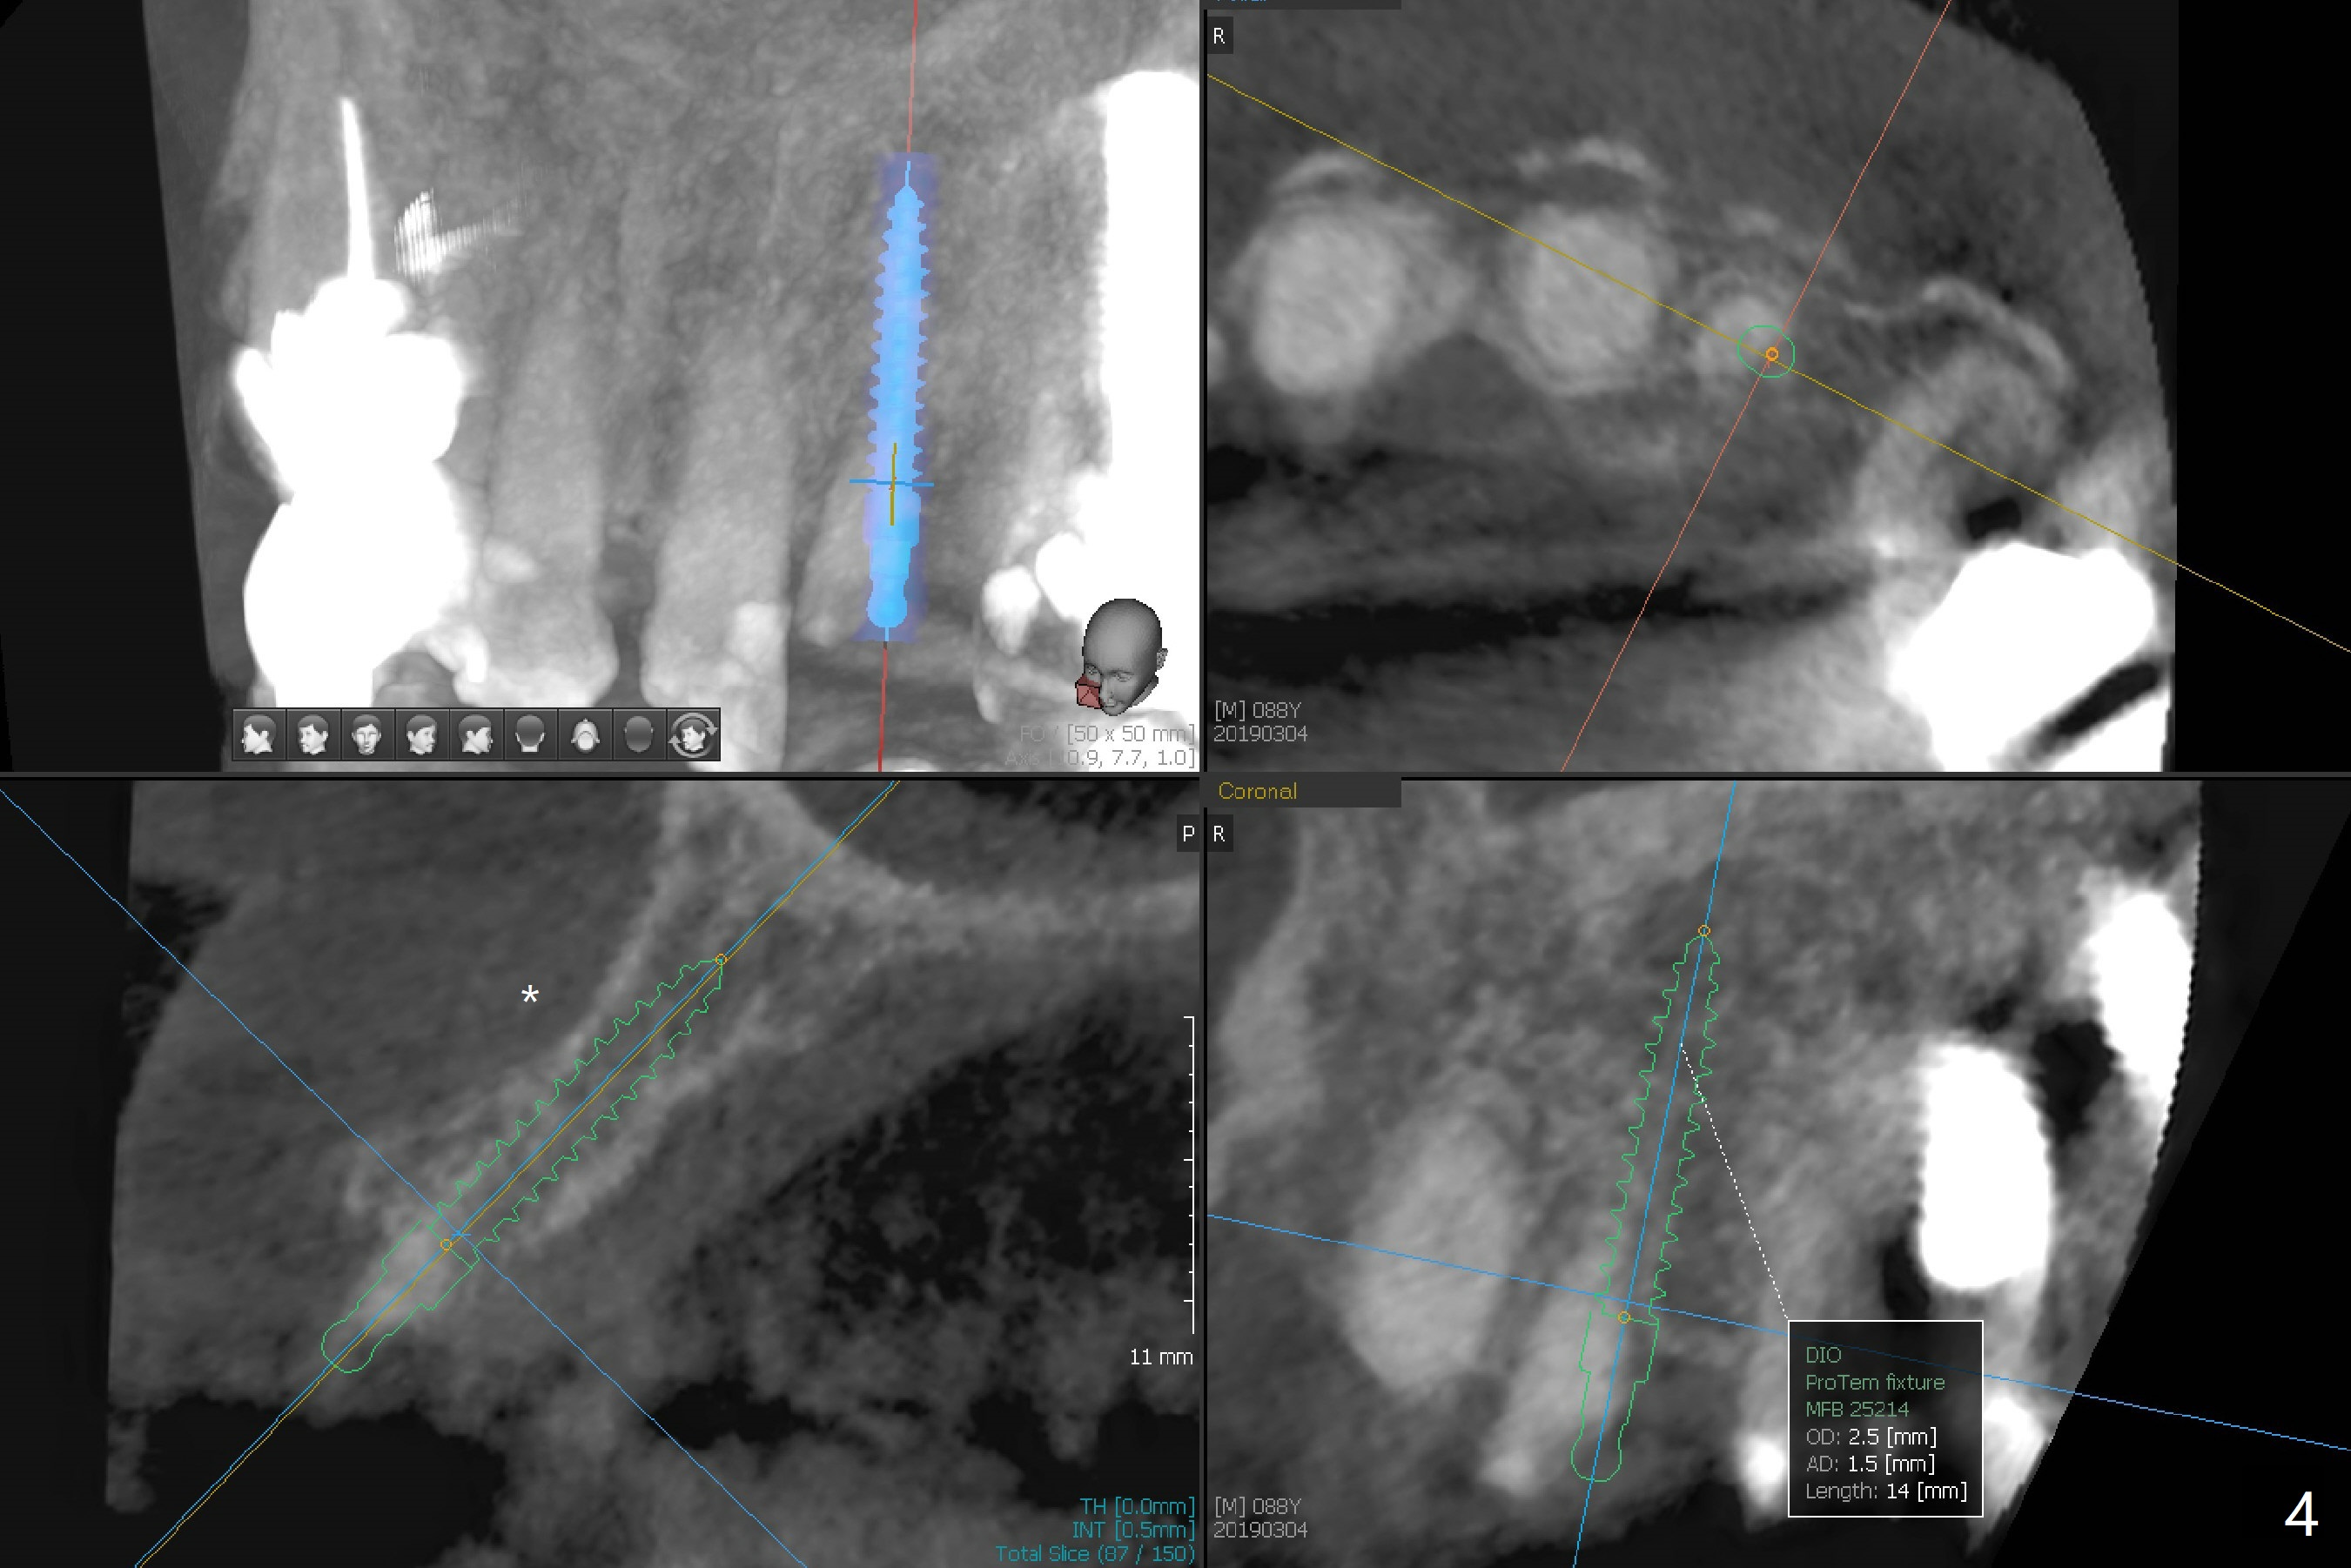

A 88-year-old man fractures the upper lateral incisor (microdontia) (Fig.1). Because of the labial concavity (white dashed line), it appears that an implant smaller than 3.5 mm is appropriate for the site. Clinical examination and CBCT confirm the concavity (Fig.2,4 *). Since the tooth deviates mesial, osteotomy should be initiated distopalatal (Fig.1,4).